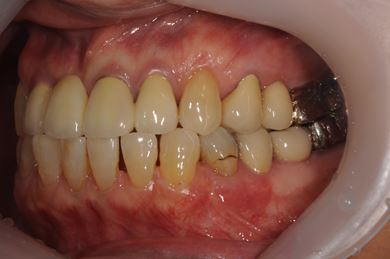

骨再生スピードインプラント治療+セラミック治療

| 治療方針 | 骨再生法によりインプラント治療を可能にする。抜歯と同時にインプラント埋入を行い、治療期間を短縮する。 | ||||||||||||||||||||||||||||||||

| 治療内容 | インプラント3本(抜歯即日スピードインプラント、GBR)、メタルボンドセラミッククラウン4本 | ||||||||||||||||||||||||||||||||